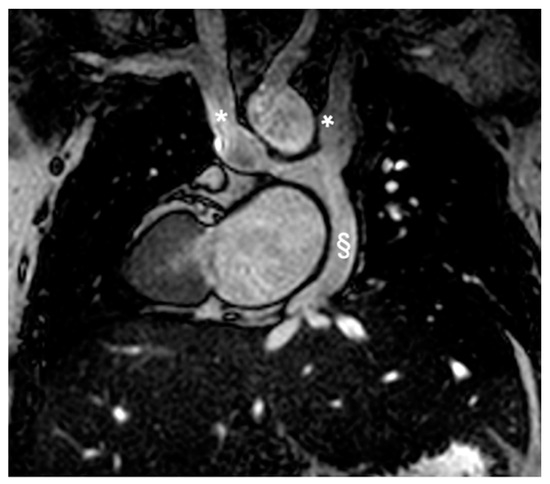

Congenital heart disease – CT/MRI – workstation-based